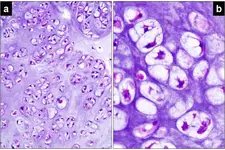

Fibröz kıkırdak, vücutta bulunan bir bağ dokusu türüdür ve özellikle dayanıklılığı ile bilinmektedir. Bu kıkırdak türü, çeşitli anatomik yapılar içinde önemli bir rol oynar ve birçok fonksiyonu vardır. Fibröz kıkırdağın yapısı, özellikleri ve işlevleri hakkında detaylı bilgiler aşağıda sunulmaktadır. Fibröz Kıkırdak Yapısı Fibröz kıkırdak, yoğun kolajen lifleri içeren bir matriks ile karakterize edilir. Bu yapı, kıkırdağın mekanik dayanıklılığını artırır. Fibröz kıkırdağın yapısal özellikleri şunlardır:

Fibröz kıkırdak, genellikle fibroblastlar tarafından üretilen kolajen tip I lifleri içerir. Bu lifler, kıkırdağın dayanıklılığını ve esnekliğini artıran bir ağ oluşturur. Fibröz Kıkırdak Türleri Fibröz kıkırdak, genel olarak iki ana türde bulunur: